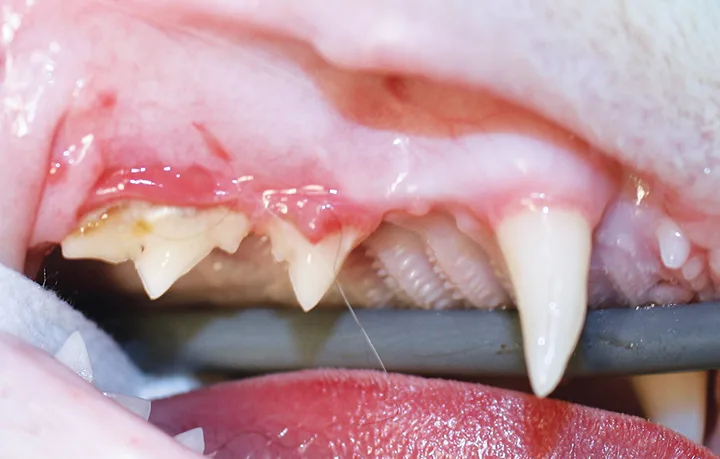

Close-up, lateral image of right cat maxilla

FIGURE 1

Significant alveolar and labial/buccal mucositis, likely associated with advanced periodontal disease, in a 5-year-old neutered male domestic shorthair cat. Radiographs are recommended to evaluate for any changes (eg, tooth resorption).